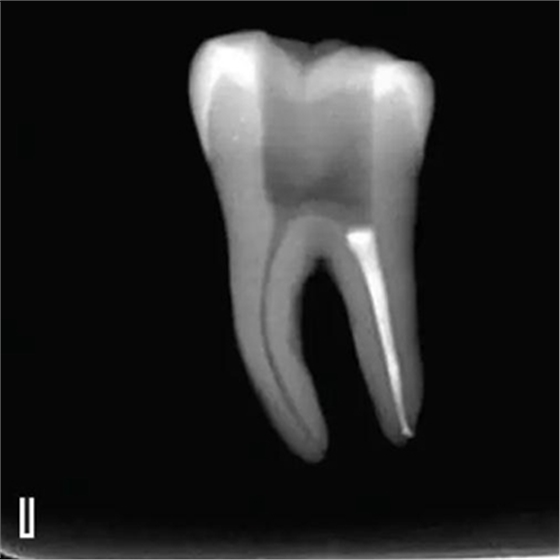

8、熱牙膠根中上段的充填

在完成根尖段的充填后,使用熱塑牙膠注射儀對根管中上段進(jìn)行分層充填,一般分2~3次完成充填,每次充填均使用相應(yīng)直徑大小的垂直加壓器進(jìn)行加壓。拍片確認(rèn)充填效果(圖8)。

圖8 熱牙膠根中上段的充填,A、B.注射儀注射中段熱牙膠

C、D.垂直加壓器加壓 E、F.注射儀繼續(xù)注射上段熱牙膠

G、H.垂直加壓器加壓 I、J.完成根中上段的充填